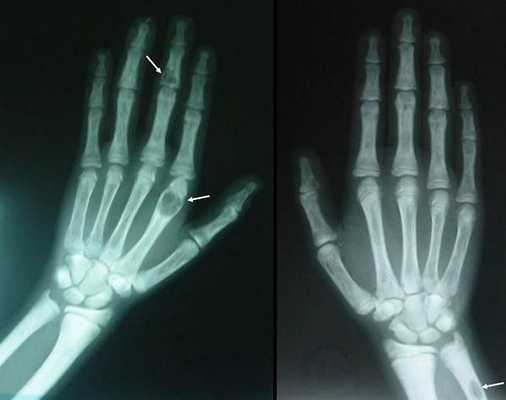

Длительное течение заболевания сказывается на формировании костей. Так, н а поздних стадиях вовремя не диагностированного гиперпаратиреоза наблюдаются:

- разрушение дистальных или концевых фаланг конечностей;

- сужение дистального отдела ключиц;

- очаги разрушения костей черепа;

- бурые опухоли длинных костей.

- Рентгенография. При денситометрии обнаруживается уменьшение плотности костной ткани, субпериостальная резорбция на концевых, средних и основных фалангах кистей. Концевые фаланги часто фестончатые, кружевные. Рентгенография почек выявляет признаки нефрокальциноза (кальцификаты).